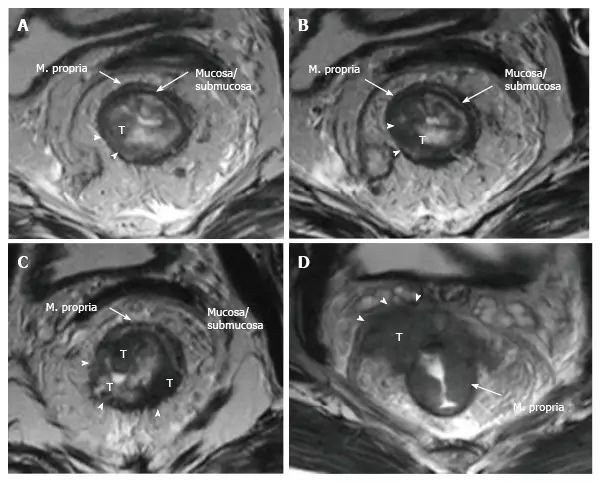

在 T2 加权成像中,固有肌层处于高密度直肠系膜脂肪和粘膜/粘膜下层之间,显示中度至轻度高信号。

T2 加权图像上的直肠肿瘤的信号强度通常介于固有肌层和粘膜的信号强度之间(图 8)。

T1 肿瘤局限于粘膜下层,T2 肿瘤向下延伸但不超过肌层,非相控阵线图条件下或直肠内超声下 T1 与 T2 的区分并不可靠,肿瘤可直接分作 T1/T2。

肿瘤超过肌层并延伸入直肠系膜脂肪时称为 T3,肌层受累时如果有穿透血管不要误将其划作 T3(图 8 和图 9)。

图 8. 直肠癌 T 分期。美国癌症联合委员会根据侵润深度进行 T3 肿瘤的分层:小于 5 mm,T3a;5~10 mm,T3b;超过 10 mm,T3c。

图 9. 直肠癌 T 分期磁共振成像。T2 加权轴向图像显示不同 T 阶段的直肠癌:A. T1 肿瘤局限于粘膜下层,尚未进入固有肌层(箭头);B. T2 肿瘤扩展到但不超出固有肌层(箭头);C. T3 肿瘤超出固有肌层和并延伸入直肠系膜脂肪(箭头);D. T4a 肿瘤侵入内脏腹膜(箭头)。

壁外侵犯深度指肿瘤超过肌层的延伸,美国癌症联合委员会建议根据壁外侵犯深度将 T3 分层:T3a<5 mm,T3b 5~10 mm,T3c>10 mm。T3a 者生存率更高,这些早期 T3 肿瘤单独手术就可控制,与 T1/T2 肿瘤预后相当。